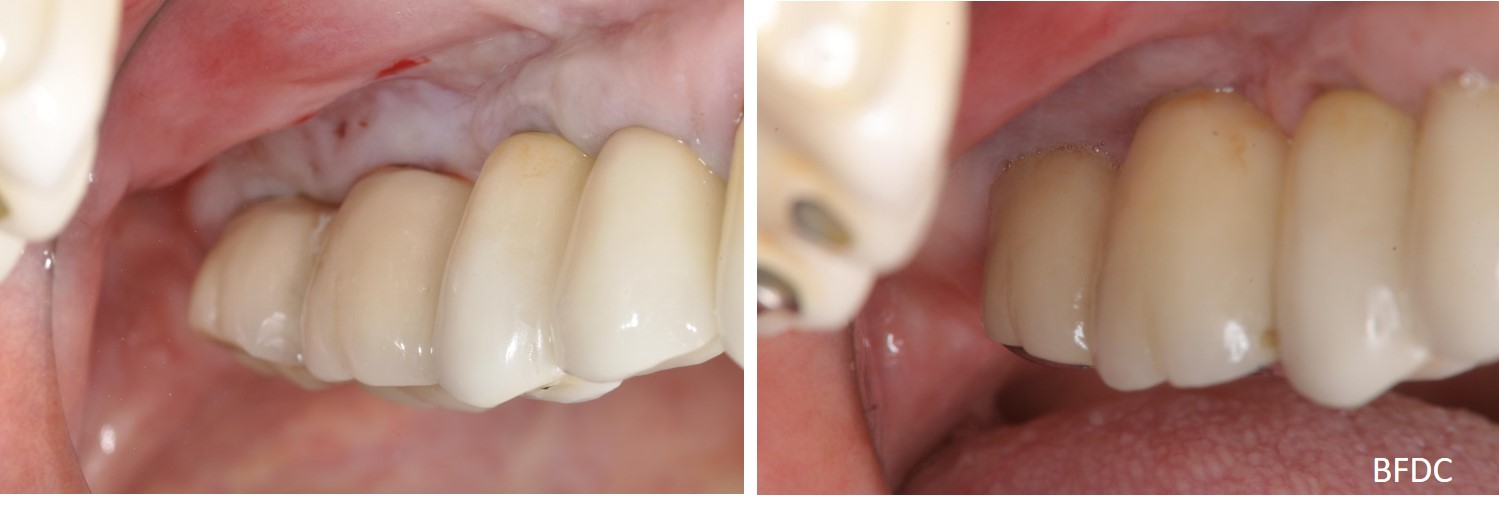

治療後口內照

治療後,植體周圍骨癒合

術前、術後比較